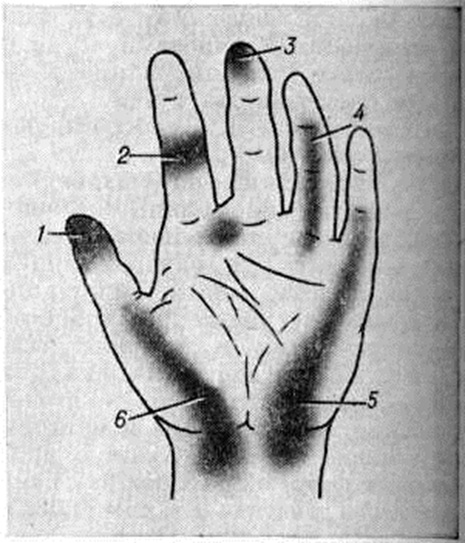

Диагноз основывается на характерном анамнезе, клинические, и рентгенологическое картине. Необходимо точно определить локализацию гнойно-некротического очага, установить фазу воспалительного процесса и клинические, форму болезни. При сборе анамнеза важно уточнить, были ли в ближайшем прошлом мелкие травмы пальцев, проводилась ли их обработка, имеют ли место факторы, способствующие возникновению гнойных заболеваний (загрязнённость рук и другие); какова давность заболевания, были ли бессонные ночи из-за болей; какое проведено лечение. При осторожном исследовании пальца с помощью пуговчатого зонда (согласно старому практическому правилу «палец пальцем не пальпируют») определяют место наибольшей болезненности, которое обычно соответствует локализации гнойного очага (рисунок 5).